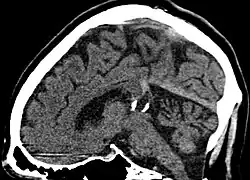

| Calcified cyst of pineal gland in CT. Sagittal MPR. |

Another case: sagittal